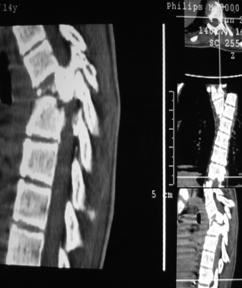

При переломо-вывихах по данным КТ отмечается повреждение всех трех колонн позвонка, смещение и дислокация тел позвонков в зоне травмы, нарушение анатомии и целостности позвоночного канала.

|

| Рис. 6. КТ признаки переломо-вывиха |